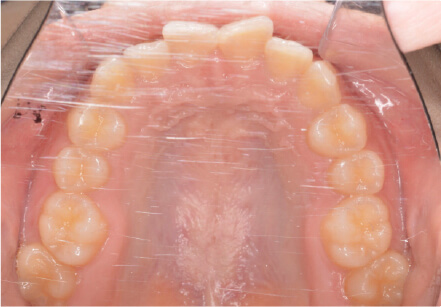

叢生の症例

10歳

/

女性

相談内容

スペース不足

カウンセリング・診断結果

myoからの移行。スペース不足のためインビザライン開始。

治療内容・方法

全額アライナー矯正

術後の経過・現在の様子

クリアライナー使用

治療のリスク

痛み・歯根吸収・歯肉退縮・虫歯・後戻り

費用・治療期間

(インビザのみ)385,000円、1年2ヶ月 + myo3年4ヶ月